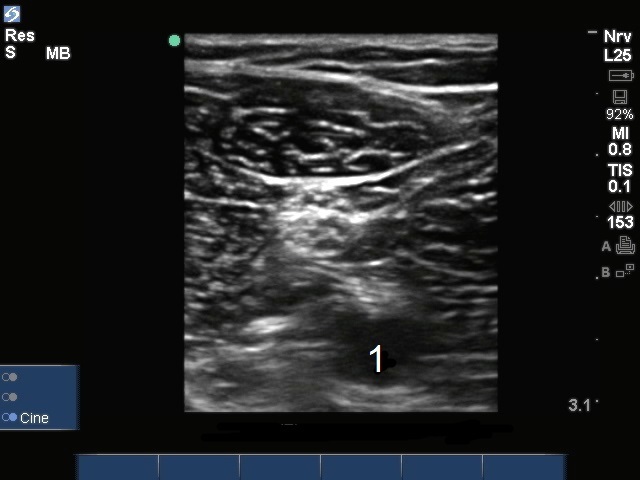

膝窩神経分岐部1画像

膝窩神経分岐部

動脈